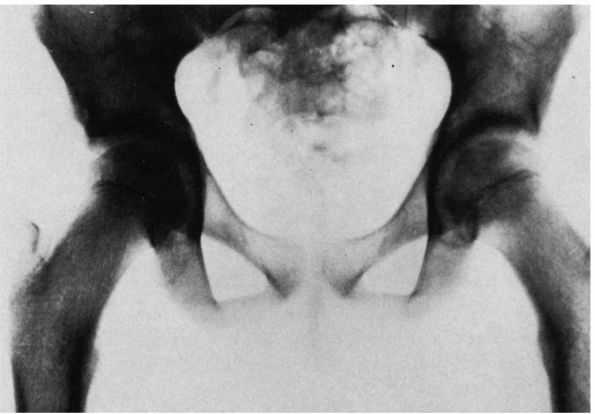

FIGURE 15-6.

Radiograph of a 43-year-old woman with complete dislocation of both hips. She has no symptoms on the right but has disabling symptoms from the left hip. She has no false acetabulum on the right but has a well-developed false acetabulum on the left with secondary degenerative changes present. (Weinstein SL. Natural history of congenital hip dislocation [DDH] and hip dysplasia. Clin Orthop 1987;225:62-76) |

institute treatment so that normal development may occur. If the hip

remains completely dislocated, its natural history depends on two

factors: the presence or absence of a false acetabulum and

bilateralness.

complete dislocations do well, maintaining a good range of motion and

little functional disability. Completely dislocated hips with

well-developed false acetabuli, however, are more likely to develop

degenerative joint disease in the false acetabulum and have a poor

clinical result (Figure 15-6). Degenerative

joint disease in the false acetabulum usually occurs in the fourth and

fifth decades of life. In bilateral complete dislocations, lower-back

pain may occur. This may be secondary to the hyperlordosis of the

lumbar spine associated with the hip flexion adduction deformities

caused by the dislocations.